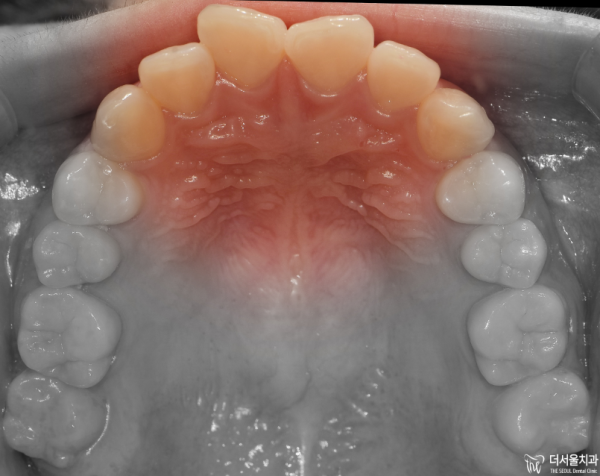

이렇게 교합면을 보면 앞니들이 위 아래 모두 삐뚤빼뚤한

총생을 보이고 있습니다.

If you look at the occlusal side, the front teeth are all crooked.

He's living his whole life.